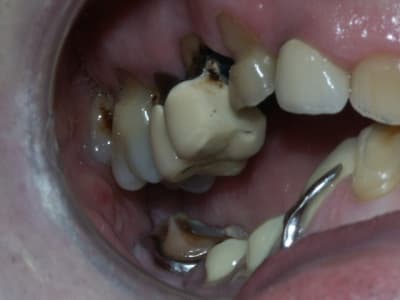

la suite...

J'ai fait une RA de 22, elle est très courte et cariée assez sous gingivale. Pas sûr du tout de la conserver.

Suis pas très chaud pour garder la 12 (LPA sous richmond)

Il y a une péche sous 26. Faut qu'on soit sûr de la garder avant de se lancer dans un bridge.

J'ai pensé aussi comme toi au bridge 32-42 mais la forme de la racine de 32 n'est pas idéale.

Le constat est le suivant, corrigez-moi si je me trompe:

on a eu des extractions non compensées à la mandibule qui ont provoquées des égressions des dents maxillaires postérieures.

une abrasion +++ du bloc antérieure avec égression "physiologique" au fur et à mesure de l'usure.

On a ainsi un décalage important (comme une marche d'escalier) de la courbe d'occlusion (Spee) entre le secteur antérieur et postérieur.

La difficulté de la thérapeutique consistera à rattraper le mieux possible ce décalage pour avoir une courbe d'occlusion "harmonieuse".